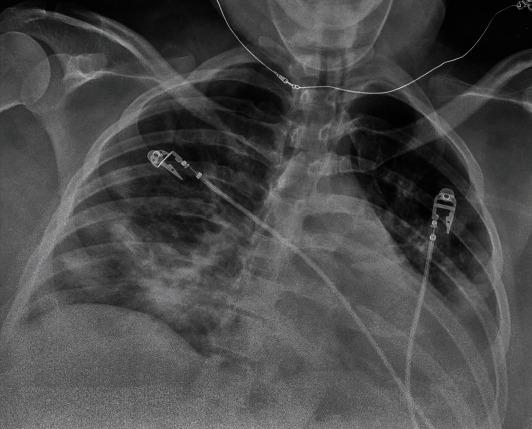

The rapidly expanding cases of the coronavirus disease 2019 (COVID-19) caused by the severe acute respiratory syndrome coronavirus 2 (SARS-CoV-2) have exposed vulnerable populations, including pregnant women to an unprecedented public health crisis. Recent data show that pregnancy in COVID-19 patients is associated with increased hospitalization, admission of the intensive care unit, and intubation. However, very few resources exist to guide the multidisciplinary team in managing critically ill pregnant women with COVID-19. We report our experience with managing a morbidly obese pregnant woman at 36 weeks' gestation with history of asthma and malignancy who presented with persistent respiratory symptoms at an outside hospital after being tested positive for SARS-CoV-2 polymerase chain reaction (PCR). Early in the course of the hospitalization, patient received remdesivir, convalescent plasma, bronchodilator, systemic steroids, and IV heparin for COVID-19 and concomitant asthma exacerbation and pulmonary embolism. Due to increasing oxygen requirements, she was eventually intubated and transferred to our institution for higher level of care. Respiratory acidosis, severe hypoxemia, and vent asynchrony were managed with vent setting adjustment and paralytics. After 12 hours from spontaneous rupture of her membranes and with stabilization of maternal status, patient underwent a term cesarean delivery for nonreassuring fetal heart tracing. The neonate was discharged on the 2 day of life, while the patient was extubated on the 6 postpartum day and was discharged to acute inpatient rehabilitation facility on the 19 hospital day. This report highlights the disease progression of COVID-19 in a pregnant woman, the clinical challenges in the critical care aspect of patient management, and the proposed multidisciplinary strategies utilizing an algorithmic approach to optimize maternal and neonatal outcomes.

由严重急性呼吸综合征冠状病毒2(SARS-CoV-2)引起的2019冠状病毒病(COVID-19)病例迅速增加,使包括孕妇在内的弱势群体面临前所未有的公共卫生危机。最近的数据显示,COVID-19患者怀孕与住院率增加、入住重症监护病房和插管有关。然而,几乎没有资源可指导多学科团队管理患有COVID-19的重症孕妇。我们报告了我们管理一名患有哮喘和恶性肿瘤病史、孕36周的病态肥胖孕妇的经验,该孕妇在SARS-CoV-2聚合酶链反应(PCR)检测呈阳性后,在外院出现持续呼吸道症状。在住院过程早期,患者因COVID-19以及伴随的哮喘加重和肺栓塞接受了瑞德西韦、康复期血浆、支气管扩张剂、全身用类固醇和静脉注射肝素治疗。由于氧需求增加,她最终插管并转至我院接受更高水平的治疗。通过调整通气设置和使用镇静剂处理呼吸性酸中毒、严重低氧血症和通气不同步。在胎膜自然破裂12小时后,随着母亲状况稳定,患者因胎儿心率监护不令人放心接受了足月剖宫产。新生儿出生后第2天出院,而患者产后第6天拔管,住院第19天出院至急性住院康复机构。本报告强调了COVID-19在孕妇中的疾病进展、患者管理重症监护方面的临床挑战,以及提出的利用算法方法优化母婴结局的多学科策略。